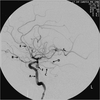

A- ICA

B- Ophthalmic

C- ACA, A1 segment

D- MCA, M1 segment

E- aneurysm

F- ACA, A2 segment

In this case the asymmetrical blood distribution is highly suspicious of a ruptured aneurysm on the right middle cerebral, posterior com- municating or internal carotid artery